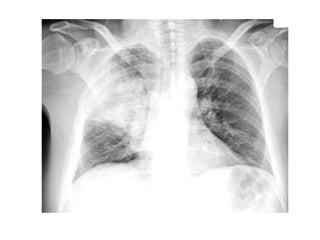

Derrame pleural tipico